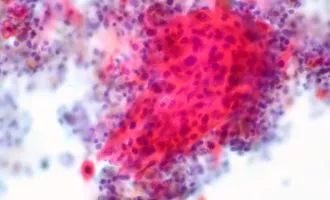

علمی کشف شیوه غیرعادی پخش شدن سلول های سرطانی در بدن [تماشا کنید]

از جهات مختلف، دشوارترین کار در مسیر مبارزه با یک سرطان، مهار آن است. از بین بردن یک تومور در اکثر موارد کار چندان بغرنجی ...

علمی آنچه که لازم است در مورد سرطان بدانیم [قسمت دوم]

سرطان مثل عمده بیماری های دیگری که ممکن است طی چند سال گذشته با آن ها سر و کله زده باشیم، عامل باکتریایی ندارد و ...

علمی آنچه که لازم است در مورد سرطان بدانیم [قسمت اول]

شنیدن واژه سرطان به تنهایی دلهره آور و ترسناک است و دلیل خوبی برای این ترس وجود دارد. سرطان، پس از امراض قلبی، دومین عامل ...